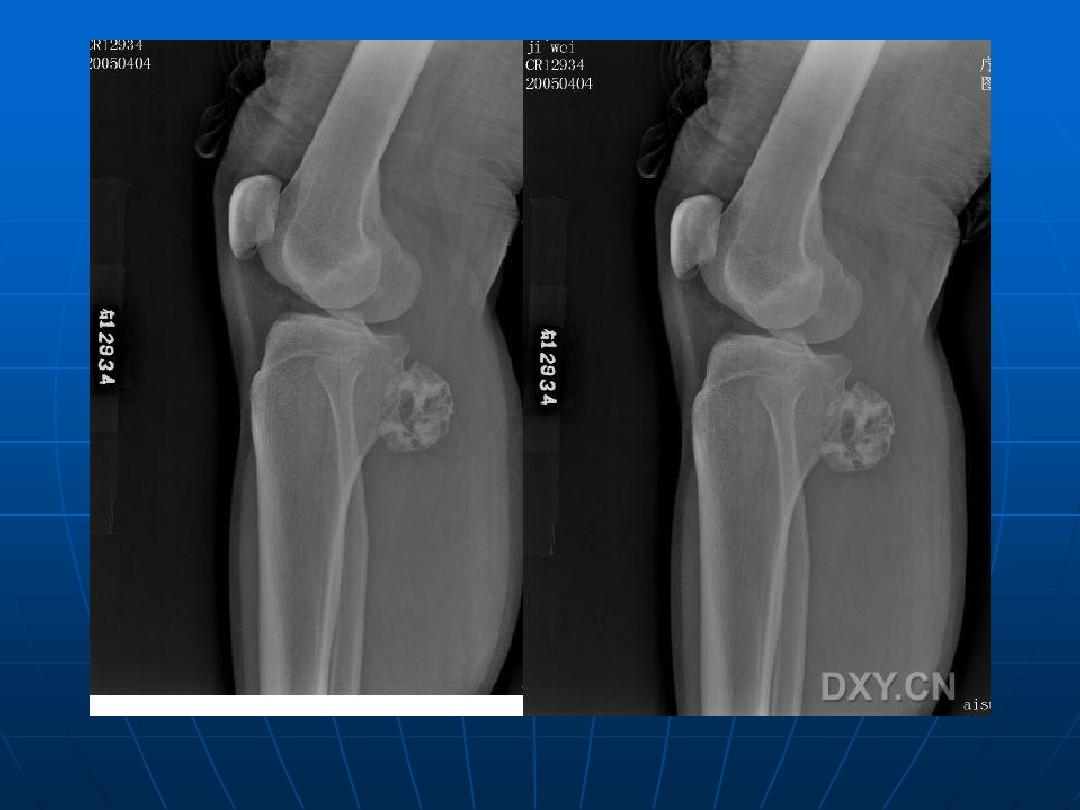

③惡變成周圍型軟骨肉瘤的發(fā)生率高。應與軟骨肉瘤,纖維肉瘤相鑒別軟骨肉瘤在x線照片上的顯影頗不一致。有時長骨的干骺端被腫瘤組織破壞而呈透明的假囊腫樣,囊內(nèi)散在少許鈣化點和骨化。有時瘤組織所產(chǎn)生的大量棉絮狀鈣化塊遮蔽著被破壞的骨缺損處,而形成致密的鈣化陰影。骨軟骨瘤的惡變起始于腫瘤的軟骨帽和其纖維包膜(參閱骨軟骨瘤),軟骨細胞分裂和軟骨鈣化作用驟然增加,以致在x線照片上發(fā)現(xiàn)多量如棉絮狀不規(guī)則的鈣化點,散在于骨軟骨瘤遠端周圍的軟組織腫塊中。放射樣的骨膜反應性新骨增生則不多見,有時或可發(fā)現(xiàn)骨膜三角。當軟骨瘤惡變時,骨內(nèi)的溶骨性陰影增大,鈣化點增多,聚集成堆。腫瘤組織有時穿透皮質(zhì)骨,在軟組織中發(fā)展并形成鈣化陰影。皮質(zhì)骨外可能發(fā)生日光放射樣骨膜新生骨反應。